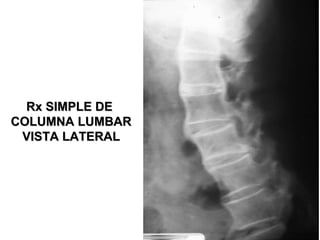

Rx SIMPLE DERx SIMPLE DE

COLUMNA LUMBARCOLUMNA LUMBAR

VISTA LATERALVISTA LATERAL

VISTA APVISTA AP